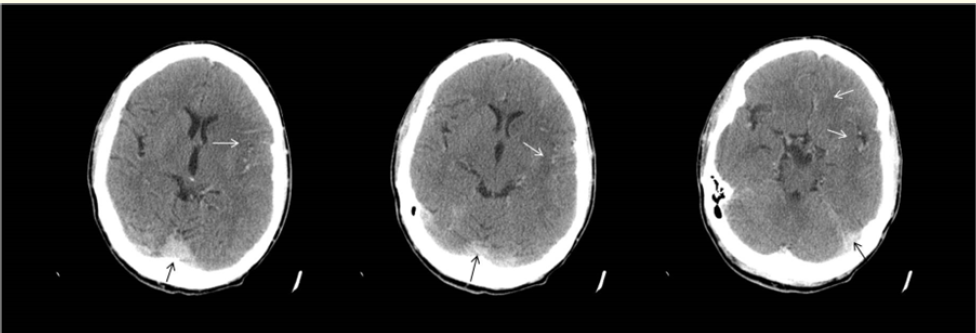

MRI Tractography Revealed an Unusual Brainstem Twisting in a Patient who Survived a Severe Traumatic Upper Spinal Dislocation

Calixto Machado, Jesus Perez-Nellar, Rafael Rodríguez-Rojas, Mauricio Chinchilla, Yanin Machado, Arthur Schift and Phillip A DeFina. 14(12): 09-12.